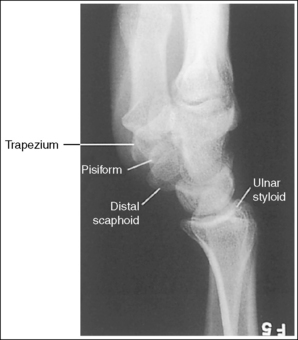

The wrist has been externally rotated to a 45-degree PA oblique projection. The trapezoid and trapezium are demonstrated without superimposition, and the trapeziotrapezoidal joint space is open. The scaphoid tuberosity and waist are demonstrated in profile. Only a small degree of trapezoid and capitate superimposition is present.

• To accomplish a PA oblique wrist projection, begin with the wrist in a PA projection, with the humerus and the forearm on the same horizontal plane. Externally rotate the hand and wrist until the wrist forms a 45-degree angle with the IR (Figure 4-35). When judging the degree of wrist obliquity, it is best to view the wrist and not the hand. The obliquity of the hand and wrist are not always equal when they are rotated, especially if the humerus and forearm are not positioned on the same horizontal plane for the image.

• Determining the accuracy of wrist obliquity. On a PA wrist projection (see Image 39), the trapezoid and trapezium are superimposed. Placing the wrist in a 45-degree externally rotated PA oblique projection draws the trapezium from beneath the trapezoid, providing clear visualization of both carpal bones and the joint space (trapeziotrapezoidal) between them. The PA oblique projection also rotates the scaphoid tuberosity and waist into profile. The relationships between the trapezoid and trapezium and the trapezoid and capitate are used to discern an accurate PA oblique wrist projection. If the wrist is underrotated, the trapezoid and trapezium are superimposed, the trapeziotrapezoidal joint space is obscured, and the trapezoid demonstrates minimal capitate superimposition (see Image 40). If wrist obliquity is more than 45 degrees, the trapezium demonstrates minimal trapezoidal superimposition, the capitate is superimposed by the trapezoid, and the trapeziotrapezoidal joint space is obscured (see Image 41).

The second CM and the scaphotrapezoidal joint spaces are demonstrated.

The long axes of the third metacarpal and midforearm are aligned with the long axis of the collimated field. The scaphoid tuberosity and waist are demonstrated in profile and are not positioned directly next to the radius.

The ulnar styloid is in profile at the far medial edge.